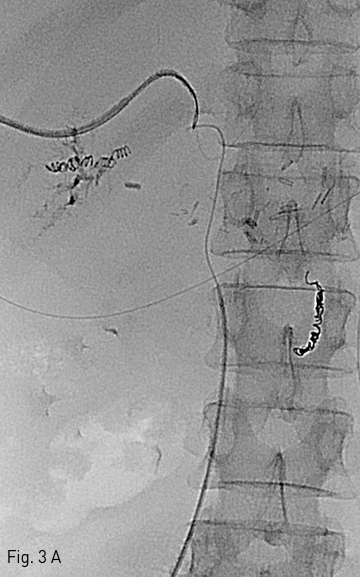

Fig 3B

(B) The stent is installed through the path of guide wire. DSA shows recanalization of the main portal vein